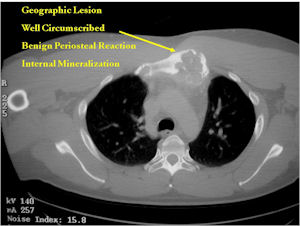

- The periosteum remains intact around the soft tissue component. Might need a CT scan to detect the subtle calcification (Egg Shell Rim of Calcification) associated with an intact periosteal reaction

- The lesion may be entirely radiolucent but usually shows some degree of mineralization. Mineralization may appear stippled like cartilage but do not see chondroid pathologically. Mineralization is sometimes better detected on a CT scan rather than an x-ray.

CT Scan:

- More useful for detecting mineralization and evaluating extent of bone destruction than plain X-ray

- Most have a similar radiographic appearance as a conventional osteoblastoma and have well defined margins, variable amounts of mineralization and peritumoral sclerosis. They occasionally have radiographic characteristics consistent with malignancy.